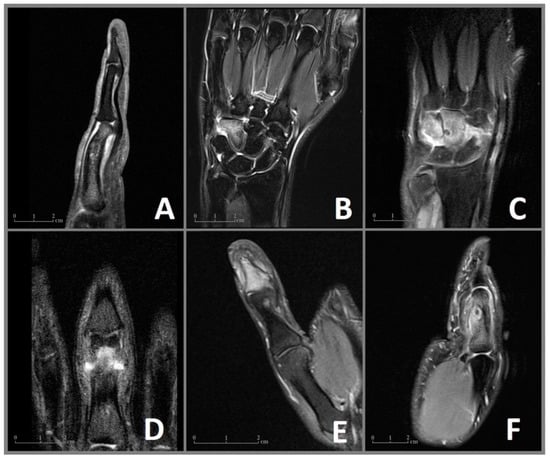

Figure 1.

MRI imaging of the OO in cases 1–6 (A–F) with visualization of the nidus and the surrounding edema of the bone marrow and the soft tissues. (A) Case 1: Sagittal MRI sequence showing the nidus in the proximal phalanx with a deformity of the affected bone and edema of the soft tissue. (B) Case 2: Coronal MRI sequence revealing an extensive bone marrow edema of the hamate. (C) Case 3: Coronal MRI sequence showing the juxta-articular nidus with extensive edema of the capitate, hamate, and an effusion of the intercarpal joints. (D) Case 4: Coronal MRI sequence showing the nidus in the proximal phalanx. (E) Case 5: Coronal MRI sequence revealing a juxta-articular nidus in the distal phalanx with an effusion of the distal interphalangeal joint. (F) Case 6: Sagittal MRI image showing the edema of the proximal phalanx, a central nidus with a reaction of the adjected periost as well as edema of the soft tissues.